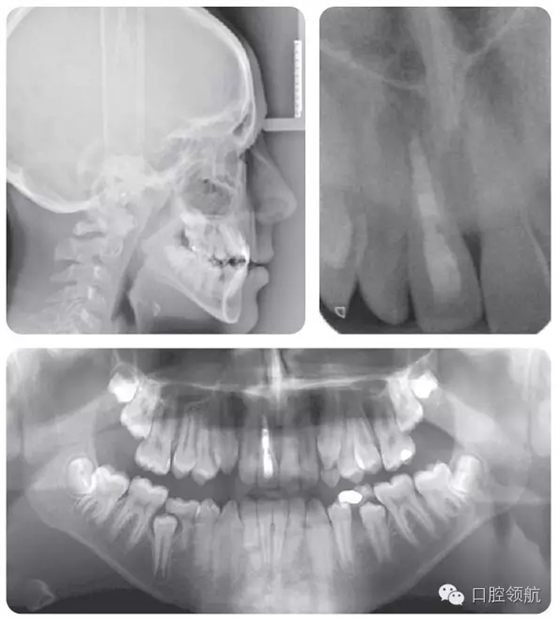

牙根外吸收可以通過牙齒的松動度來判斷。在一些病例可能發(fā)生根骨粘連,并且牙齒位置較鄰牙常表現(xiàn)為未能萌出至平面。叩診該患牙呈高調(diào)、濁音。正畸力往往難以使該牙產(chǎn)生移動。臨床和X線片檢查(圖2.47)顯示該患者的UR1發(fā)生了根骨粘連。

● UR1根骨粘連,牙冠變色。